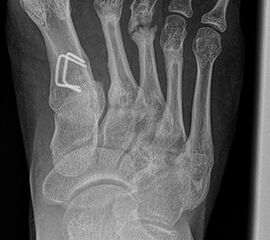

Schneiderballen: MT V Osteotomie

Diese Osteotomie ist indiziert bei stark lateralisierten MT V Köpfchen wie es nicht selten in Kombination mit einem Hallux valgus, einem Ballen-Hohlfuß oder Klumpfuß vorkommt (Abb. 25).

Abb. 25: Prominentes MT V Köpfchen, eine sogenannte Schneiderballen-Deformität.

Dementsprechend führen wir die MT V Osteotomie häufig als Kombinationseingriff durch. Sie kann subcapital im Sinne der Kramer-Osteotomie oder adduzierend am Schaft durchgeführt werden (Abb. 26).

Abb. 26 a-e: adduzierende Osteotomie. (a) Fuß präoperativ d.p. und (b) als Schrägaufnahme. Im Schrägbild gut sichtbar die subluxierte 5. Zehe. (c) intraoperative Aufnahme der MT V Schaftosteotomie. (d) Fuß postoperativ d.p. und (e) als Schrägaufnahme.